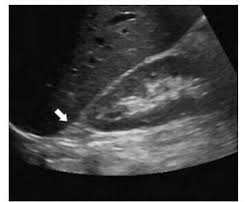

Kidney Ultrasound Adrenal Glands. It s hard to see normal adult adrenals on ultrasound despite being near the kidneys review of the adrenals in an adult is not part of the routine kidney ultrasound. An outer cortex and an inner medulla.

Details of the adrenal glands. High resolution real time sonography allows visualization of normal adrenal glands in 71 92 of adults. The normal ascent of the kidneys allows the organs to take their place in the abdomen below the adrenal glands. The left adrenal gland is imaged by a posterolateral approach in coronal plane through the long axis of the left kidney.